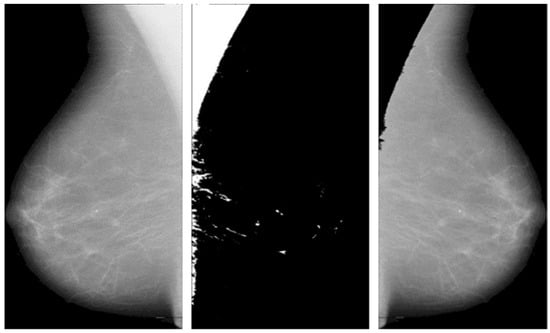

The DL model is implemented in this paper for the segmentation of breast and pectoral muscle removal. The mammogram image is presented in Figure 1. To identify the pectoral muscle, image pre-processing is essential to eliminate noise and artifacts from a mammogram image. This proposed methodology consists of three stages: (i) image de-noising, (ii) breast segmentation, and (iii) pectoral muscle extraction. The raw mammogram image is usually contaminated with numerous noise sources. Elimination of noises from a mammogram image increases the overall system performance. The second and third stages represent breast segmentation and pectoral muscle extraction. The pectoral muscle removal process is as follows; grayscale conversion simplifies the image to one channel, making processing easier.

This operation keeps the pixel values of the original image where the mask is black and sets them to zero where the mask is white. The process is automated to handle multiple images and save the results efficiently. The following Figure 2 shows the significance of pectoral muscle removal.

4.1. Artifact Removal and Breast Region Segmentation

The artifacts cover an average of 70% of the area of the mammogram, and the remaining 30% area only covers the breast region. In this stage, artifacts are removed with threshold and morphological operations. The initial step of region segmentation is conversion of grayscale image to a binary image. Binarization is accomplished with the Otsu threshold technique. From the connected component labeling, the largest pixel (component) is selected, and the remaining components are removed to produce higher accuracy and reduced execution time, the breast region is extracted, and further analysis is performed with this extracted region. Figure 3 and Figure 4 show the artifact removal and breast region segmentation.

The final stage of pre-processing is elimination of pectoral muscles from the mammogram image. Contingent upon the image orientation, pectoral muscle will be positioned in the upper left or upper right corner. Tissue density and the dense area of pectoral muscle are tightly associated, and this relationship may influence subsequent mammography analysis. Pectoral muscle detection and removal are crucial steps in the pre-processing of mammograms.